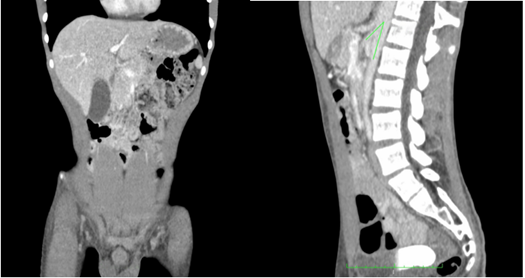

El paciente tuvo una mejoría clínica y anímica evidente, sin vómito ni dolor abdominal y desapareció la ictericia. Un mes después se decidió tomar una TC de control, en la cual se observaba desaparición del aire en la porta y retorno del estómago a su tamaño normal, con desaparición de la neumatosis en la pared; había aumento del ángulo aorto-mesentérico a 28,9 grados en el corte sagital, con paso del medio de contraste al íleon distal y aumento de la distancia aorto-mesentérica a 5,2 mm en el corte axial (Figura 2).